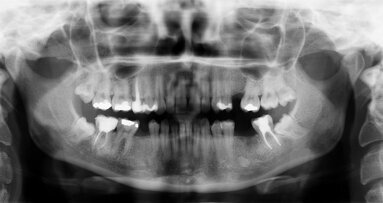

Ośrodek Kształcenia Naczelnej Izby Lekarskiej zaprasza na kurs pt.: „Obrazowanie 2D w stomatologii”, który odbędzie się 21.01.2023 r. (sobota) w ...